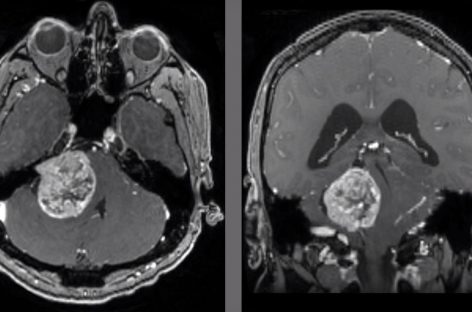

Studiu: Celulele imune lasă amprente în tumorile care metastazează în creier, oferind indicii pentru noi terapii 21 feb 2022